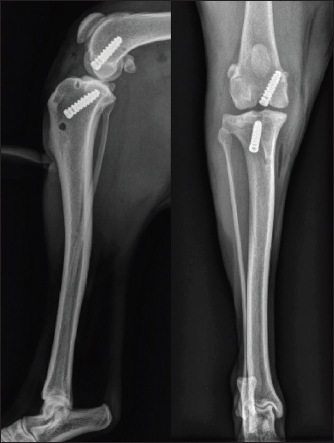

Postoperative radiographs showed a satisfactory position of the tunnels and a good implantation of the interference screws along the drilling axes (Fig. 5).

Fig. 5. Immediate postoperative radiographic views of the dog's right pelvic limb from side (left) and front (right).